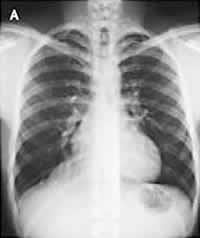

1名20岁的海军学校学生,在军队体格检查时被发现其胸部X线片异常,而来心脏科门诊。其自诉无症状,体格检查结果亦正常。X线胸片(图A)显示在右心膈角区有一平滑的密度边缘,它部分地遮盖了右心边界。CT扫描显示(图B),紧靠心脏的右边界有一均质的平滑病灶,其间没有分隔和钙化。大小约5.0 cm×4.4 cm×7.0 cm,而心脏和大血管均正常。超声心动图(图C)对该病灶进行了进一步评价,改良右胸骨旁角度证实存在一个充满液体的心包囊肿。由于该军校学生没有症状,并且心包囊肿是良性的,所以医师决定对其临床随访观察。